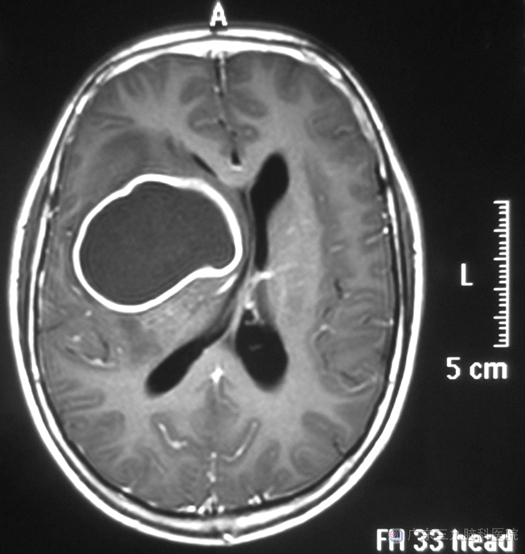

小徐一天前出现头部钝痛,疼痛部位不固定,难以忍受,不能缓解,伴有呕吐数次。家人担心脑袋了长了肿瘤。立即送他去当地医院检查,头颅CT检查提示右侧额叶、基底节区巨大占位性病变,广东三九脑科医院头颅MR检查:右侧基底节区示一囊状占位性病变,大小约为62.4mm×44.9mm×45.0mm,中线结构向左偏,考虑脑脓肿可能性大。

由鲁主任主刀,在唤醒麻醉下行右侧额叶、基底节区脑脓肿壁部分切除术,术中导航定位,显微镜下见脓肿壁与脑组织粘连严重,分离困难,切开脓肿腔,吸引器吸除残余脓液,冲洗脓肿腔,沿脓肿壁分离分块切除,过程顺利。术后病理:脑脓肿。